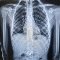

בשבוע שעבר, בשעות הלילה המאוחרות, הגיע י' יחד עם משפחתו למלר"ד ילדים במרכז הרפואי שערי צדק לאחר שבלע להבי מספריים באורך של שלושה ס"מ. לאחר צילום הרנגטן בו נראו המספריים כאשר הלהבים נמצאים במצב פתוח בקיבה, הוזעקו צוותים רפואיים בתחומי כירורגיית וגסטרו ילדים, לרבות מומחה לפרוצדורות אנדוסקופיות בילדים בשערי צדק, ד"ר אורן לדר, והוחלט להכניס את י' לחדר הניתוח באופן דחוף כדי להוציא את המספרים.

כשי' נמצא בהרדמה מלאה בחדר הניתוח, בוצע צילום נוסף כדי לבחון את מיקום ומצב המספרים. בצילום התברר כי המספריים נסגרו מעצמם, עברו את הקיבה והגיעו לעומק המעי הדק. "הייתה סכנה שהמספריים הפתוחים יגרמו לפציעה לושט או לקיבה ורצינו לבצע בדיקה על מנת לאתר ולשלוף אותם", אומרת ד"ר אסתר אורלינסקי-מאייר, מומחית בגסטרואנטרולוגיה ילדים בשערי צדק. "באורח פלא ומסיבה לא ברורה, ראינו שהמספריים נסגרו מעצמם, כך שהסכנה לפציעה בדרכי העיכול פחתה".

בתמונות:

צילום המספריים במצב פתוח בקיבה ובמצב סגור במעי הדק.